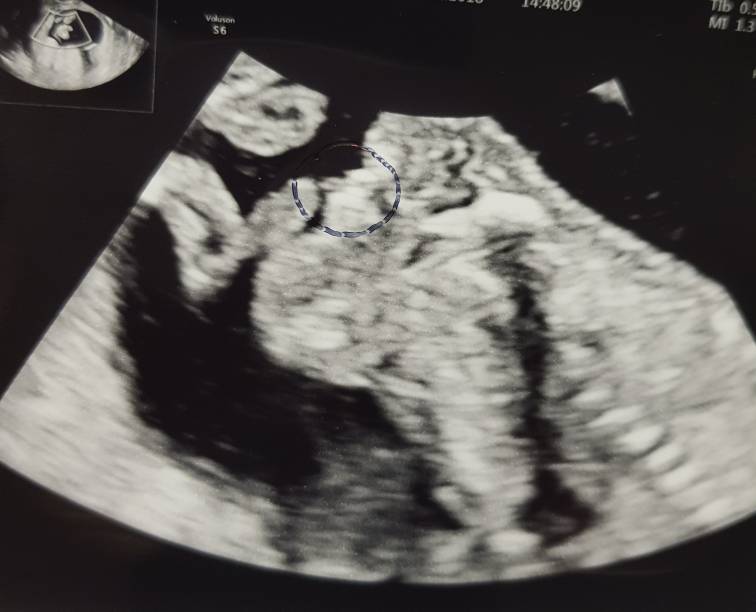

) córeczka potwierdzona na 100%, poniżej dowody i paluszki małej pianistki [emoji3]

Jestem trochę spokojniejsza po wizycie, lekarz obejrzał maluszka bardzo dokładnie, nie widział żadnych nieprawidłowości, odradził aminopunkcję - robi to zawsze kiedy ryzyko powikłań jest większe od ryzyka choroby, które podkreślał, że jest niskie. Test Nifty kazał już samodzielnie rozważyć, on gwarancji na zdrowe dziecko dać nie może ale nic nie budzi jego niepokoju. Muszę to spokojnie przemyśleć.

A tu moja Pchełka